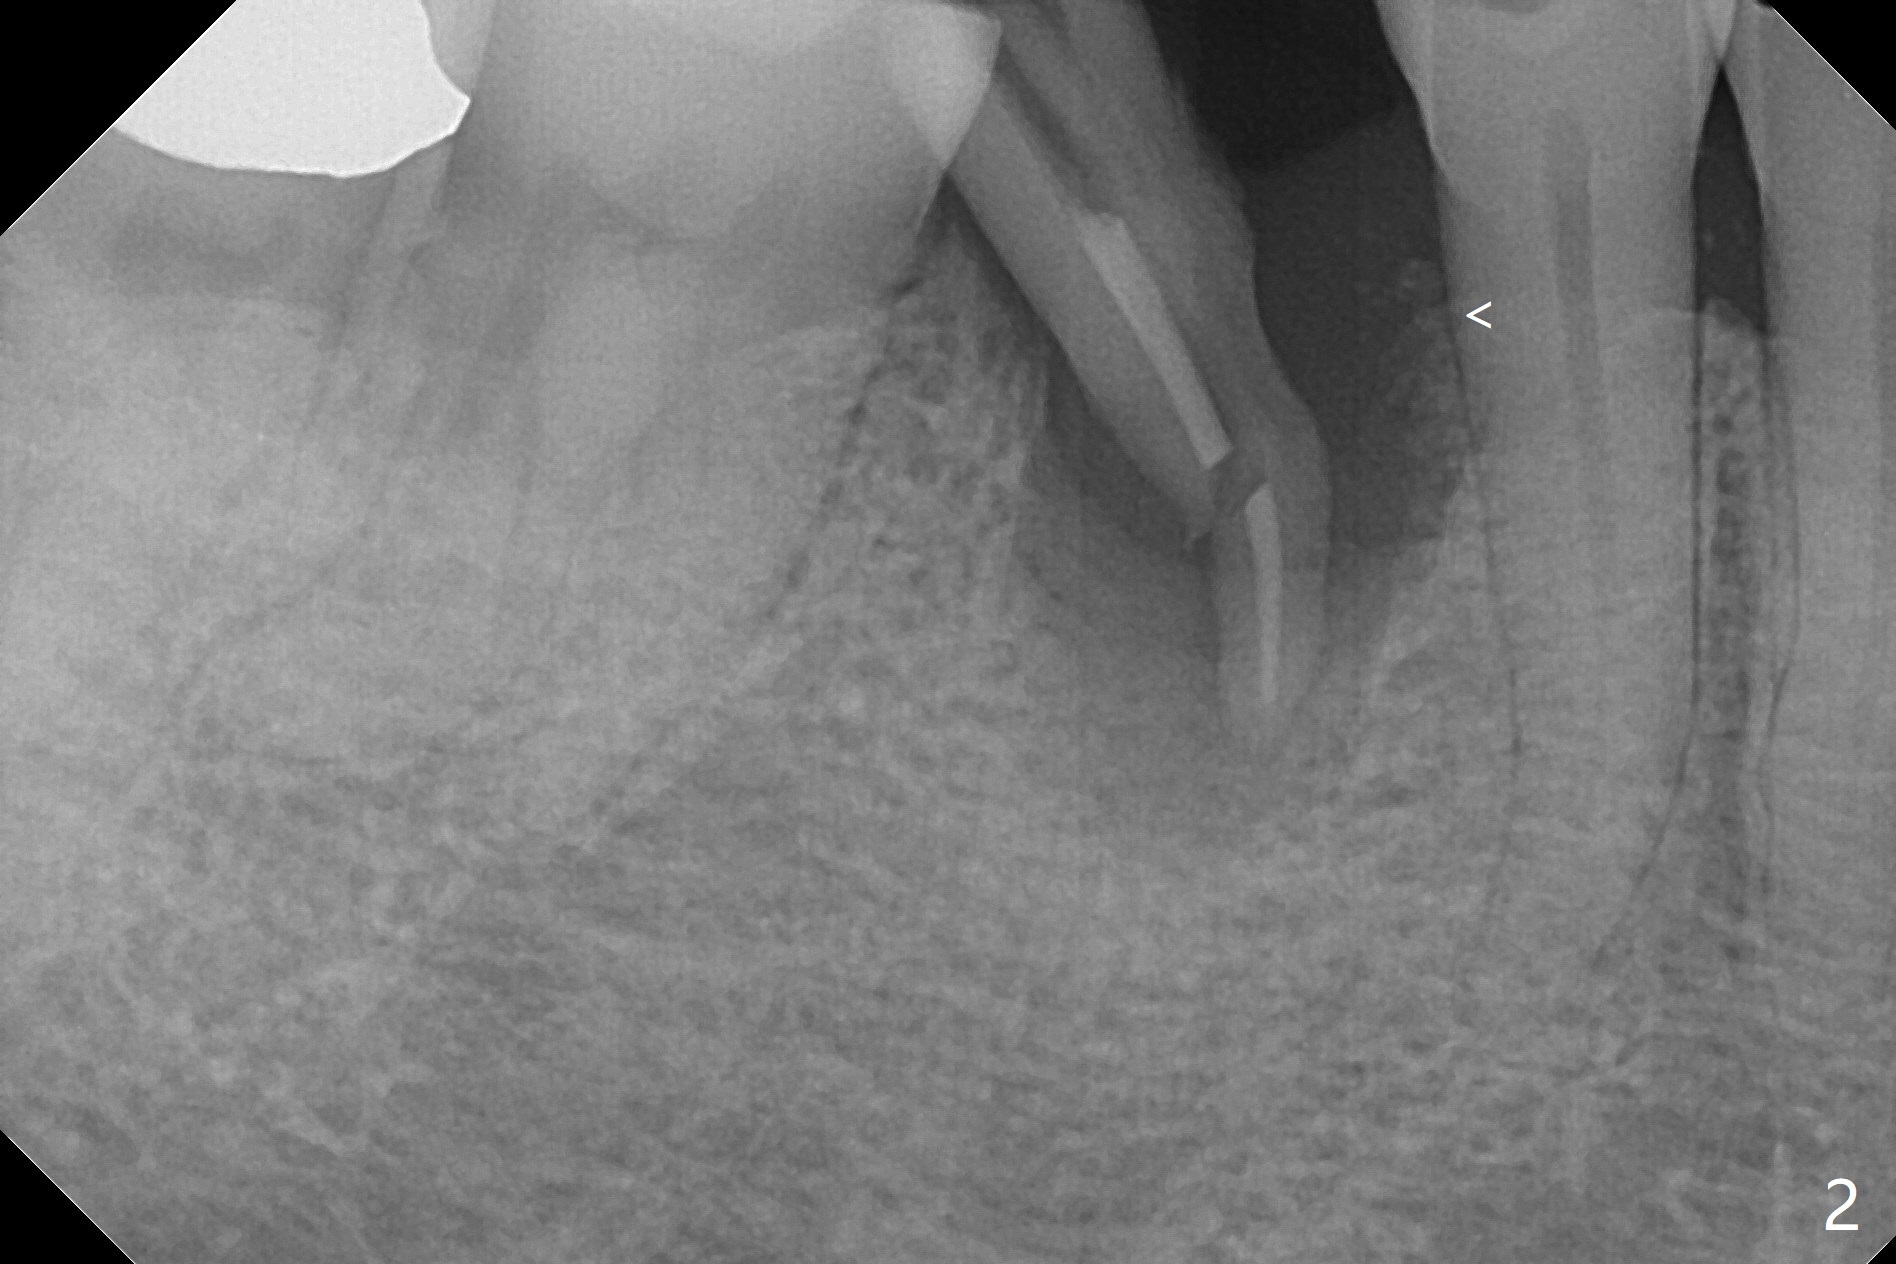

A 77-year-old woman agrees to have the lower right 2nd premolar extracted after lengthy delay (Fig.1,2 buccolingual plate present, but low) and grafted (Fig.3 *).  Cortical graft is heavily packed, covered by a small piece of 6-month membrane and sutured with 4-0 Chromic gut suture.  The socket is closed 7 days postop (Fig.4).   The buccal plate seems to have been reformed 6 months postop (Fig.5,7, as compared to Fig.6 (pre-fracture)).  Return to No Deviation Surgery  Xin Wei, DDS, PhD, MS 1st edition 08/19/2020, last revision 05/12/2021